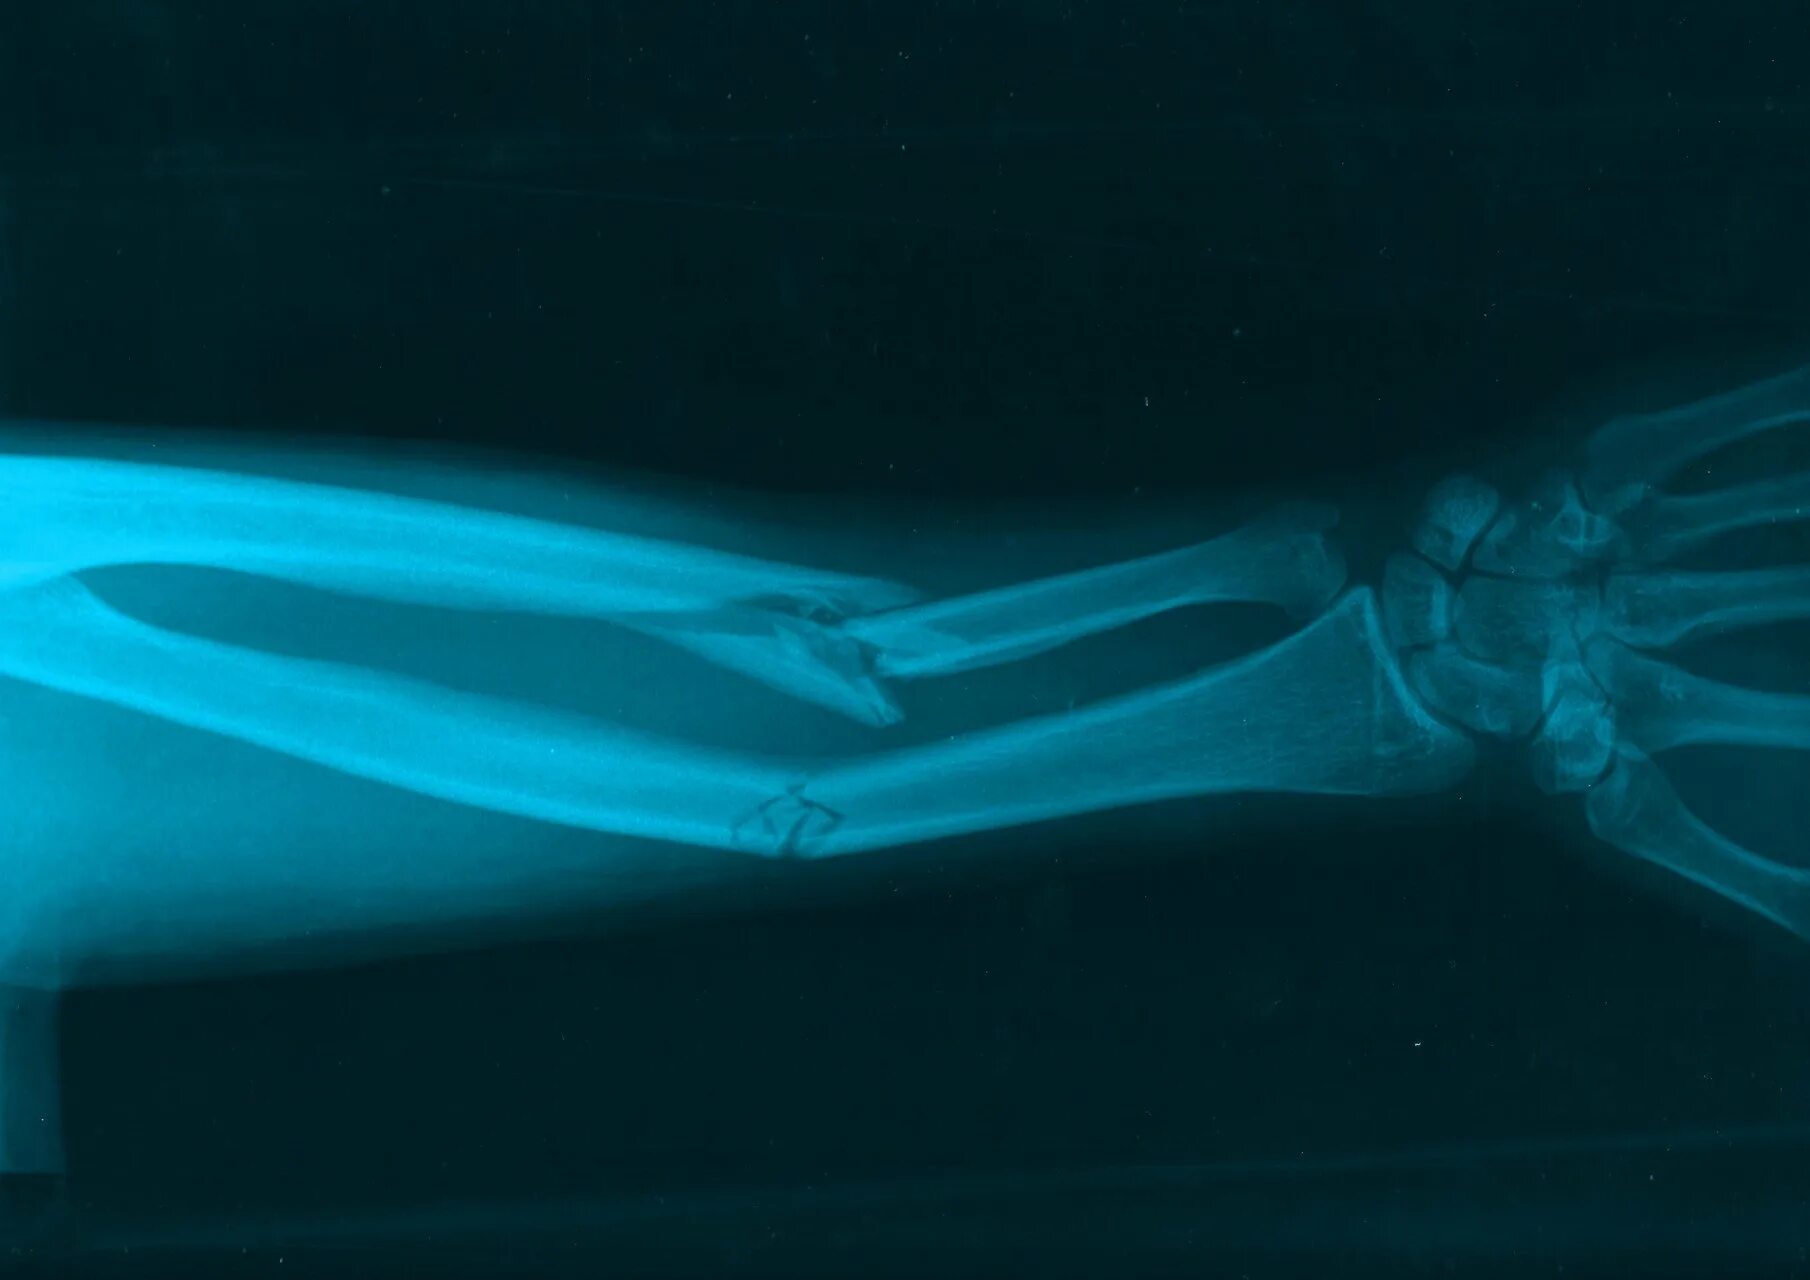

Фото переломов костей